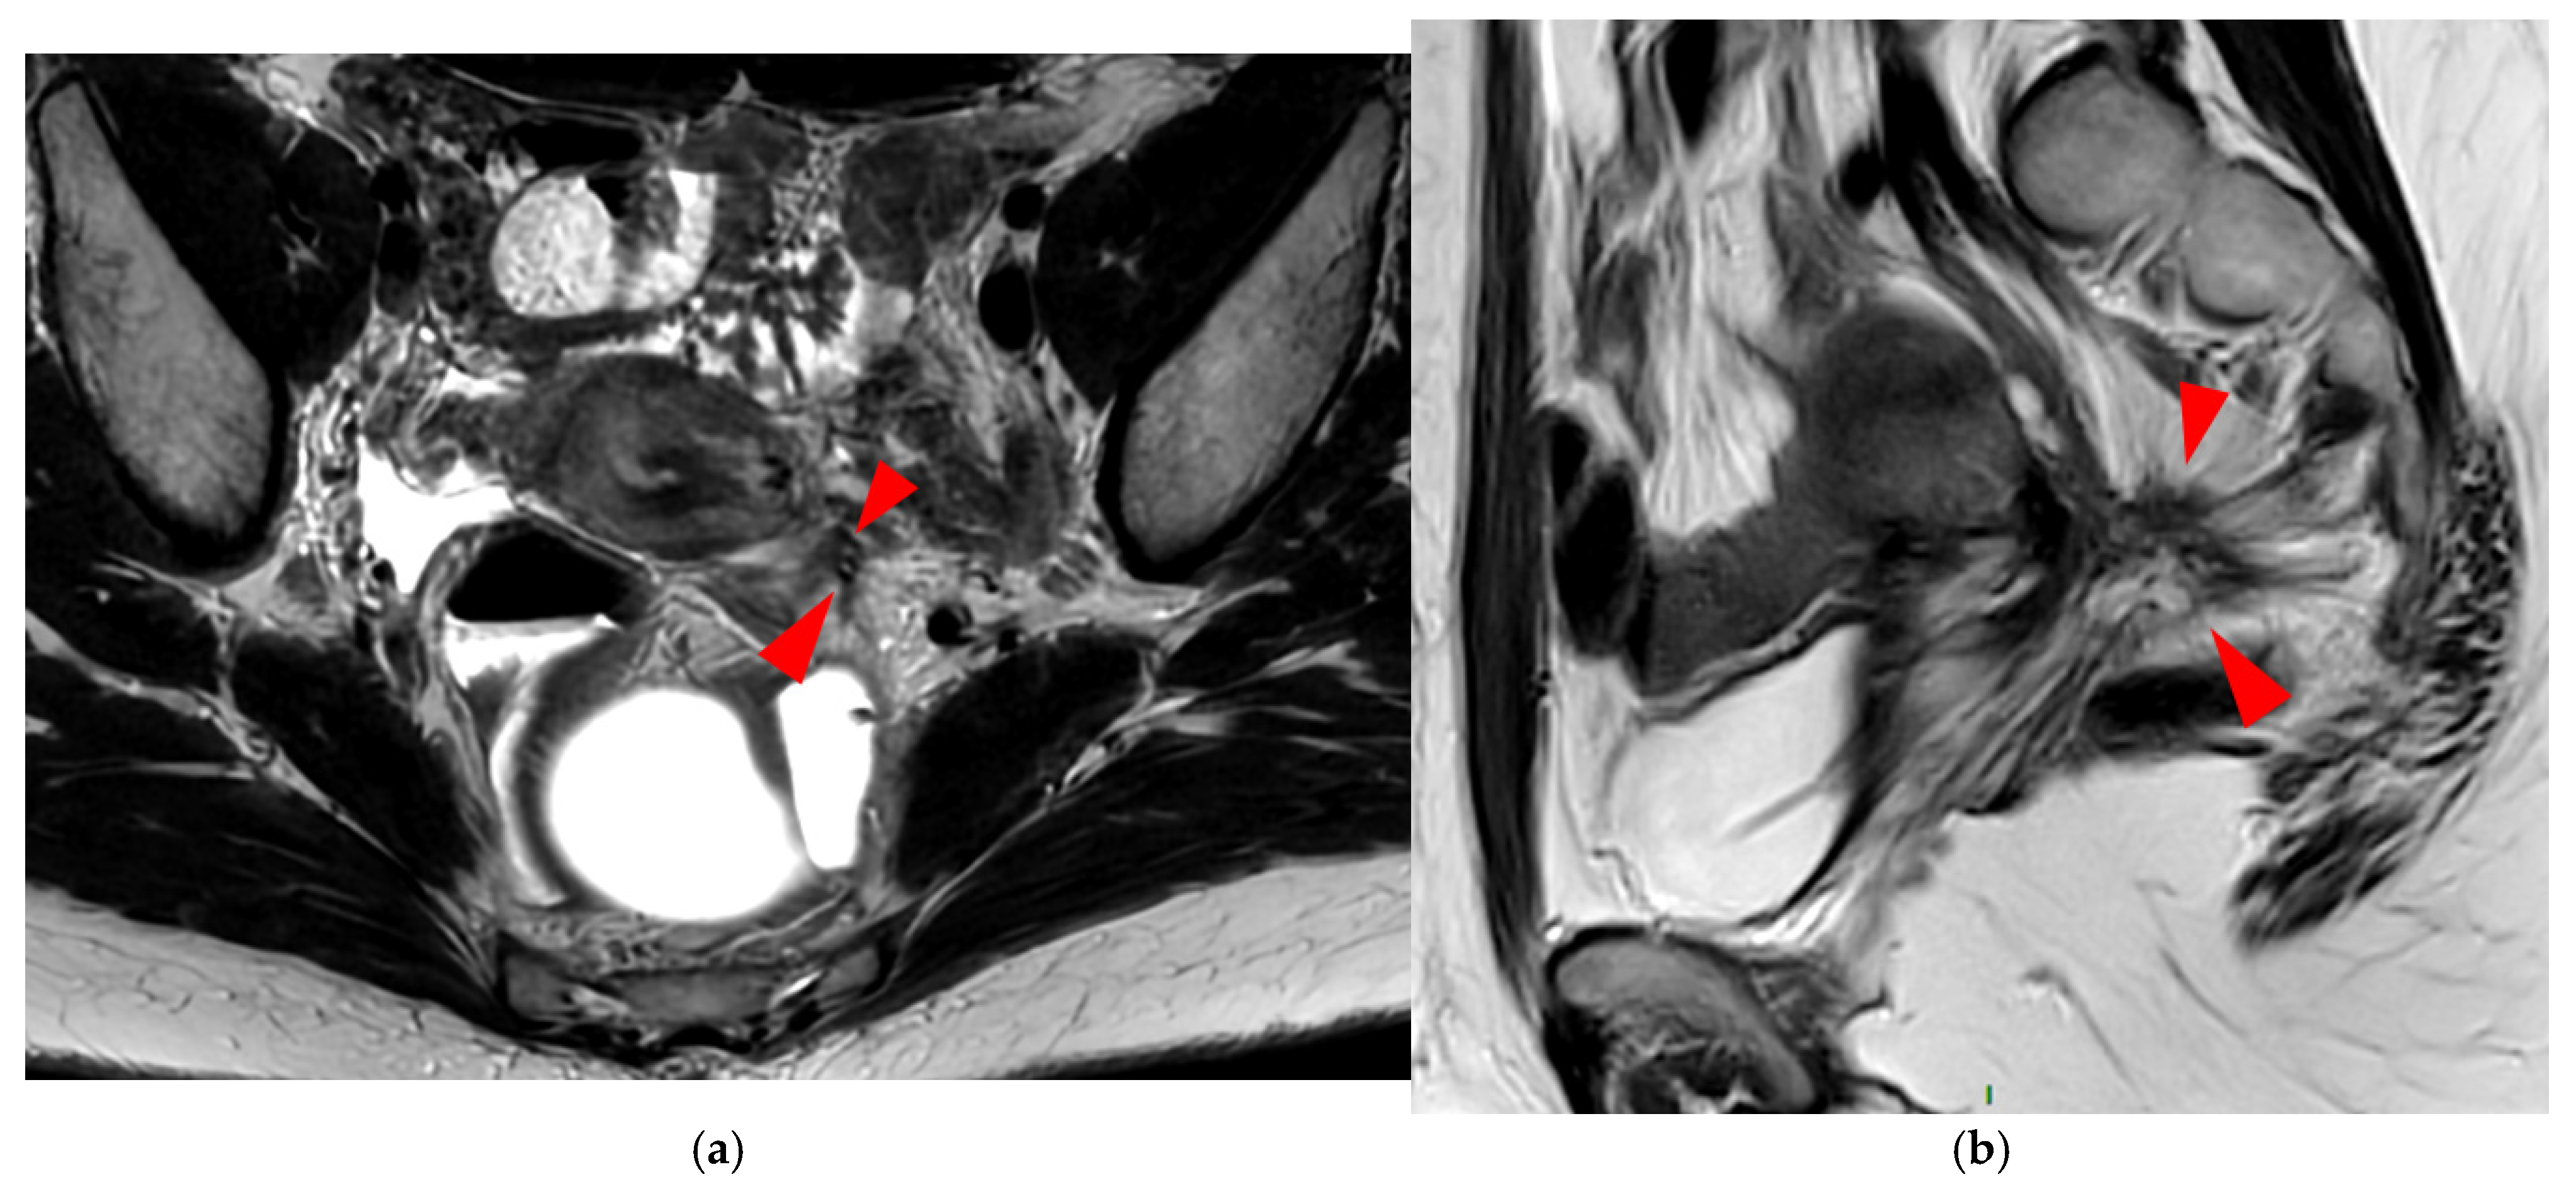

Figure 14. Pelvic MRI scan of a patient with a HTD type 6 USL. (a) Axial T2WI shows a visible but thin (1.6 mm) left USL (dashed arrow) and a thick (3.5 mm) but smooth right USL (arrowhead), initially classified as a type 2 left USL and a type 3A right USL. (b) Axial fat-suppressed T1WI reveals hyperintense hemorrhagic spots within the left sciatic nerve (arrow). (c) Axial T2WI demonstrates spiculated nodularity within the left sciatic nerve (arrow), leading to reclassification as type 6 left USL due to this so-called “visceral” nerve involvement. Note the neurogenic amyotrophy (red star) of the left piriformis and gluteal muscles, including the gluteus maximus, gluteus medius, and gluteus minimus.

A type 6 USL is associated with adjacent pelvic “visceral” involvement in a broad sense. It most commonly affects the digestive tract (Figure 8 and Figure 9), with the rectum and rectosigmoid junction wall thickening: in this case, the lesion often appears as a “medallion-shaped” protrusion into the lumen. Less frequently, the urinary tract is affected (Figure 9 and Figure 10), involving the muscular layer of the bladder or even the distal ureter at the level of the common iliac artery, with stenosis potentially leading to upstream hydronephrosis. More rarely, as USLs are also close to nearby pelvic nerve structures (Figure 11), contiguous involvement of the inferior hypogastric plexus located in the sacro-recto-genital septum (a.k.a. Delbet sagittal fascia) beneath the distal two-thirds of the USL, or exceptional involvement of the sciatic nerve adjacent to the pelvic wall, is possible (Figure 12, Figure 13 and Figure 14).